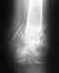

Получил травму правой руки Упал на руку двутавр около 2х тон весом При падении двутавр протянул руку сантиметров 15

Упал на руку двутавр при этом накрыло руку до средины локтевого сустава Рука напоминала форму ласты но при этом сломался только большой палец он угодил под ребро двутавра благо упал он с небольшой высоты Но палец сростался 8 месяцев теперь имею проблему такую при сгибании боль в запястье на руку не могу облокотится сылы нет вруке постоянно отекает рука очень реагирует на погоду тепло холод не могу надеть даже часы на руку сразу отекает хотя браслет свободный о обручальном кольц не говорю сразуже отекает палец и снять очень тяжело частенько бывают прострелы в сторону локтя болят все фаланги пальцев и ощущения руки как будто она не моя врачи говорят все у тебя хорошо ты просто не хочеш работать вот уже нахожусь 14 месяцев на больничном последнее мое достижение жим динамометра 26 кг Уменя вопрос что смоей рукой Я нахожусь в Испании много чего не понимаю подскажите пожалуйста какие могут быть последствия такой травмы Спасибо